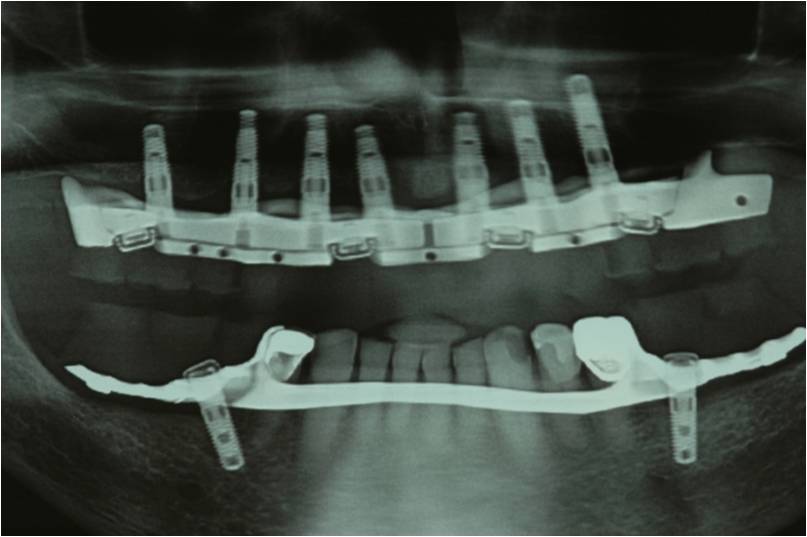

עקב חוסר בעצם ואי רצון מצד המטופל לעבור הרמות סינוס בוצע תיכנון ממוחשב של מיקום השתלים עוד בטרם ההשתלה.

ההשתלות בוצעו דרך שבלונה שהוכנה במדפסת תלת מימד בהתאם לקובץ הממוחשב.